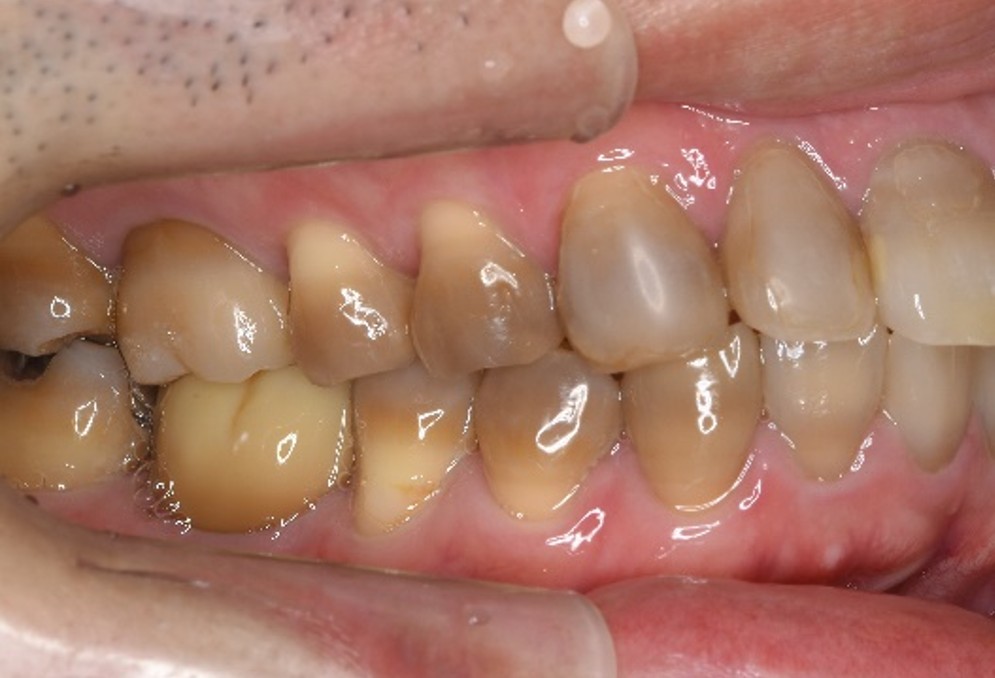

治療前

治療後